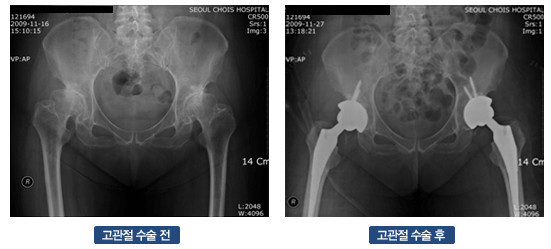

고관절 수술 후 회복 기간은 환자의 상태와 수술 방법에 따라 크게 달라집니다. 일반적으로 고관절 수술에는 두 가지 주요 유형이 있습니다. 첫째는 관절경 수술로, 최소 침습적으로 문제를 해결하는 방법입니다. 이 경우 회복 기간이 짧을 수 있습니다. 둘째는 관절 치환술로, 고관절을 인공 관절로 대체하는 수술입니다. 이 수술은 보다 복잡하며, 회복 기간이 상대적으로 더 길어진다는 특징이 있습니다.